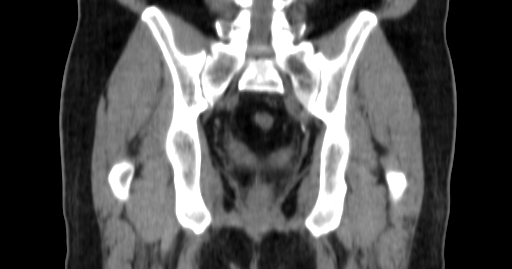

ClearRT® Images

Imaging Information

ClearRT®

Protocol

Pelvis-normal-FOV50cm

Scan Length

9 cm